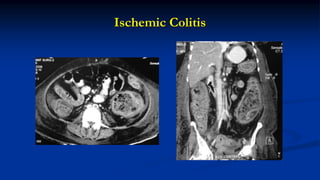

Ischemic Colitis

 Colitis: ischemic, infective, pseudomembranous, UC, Crohn’s

 An empty colon sign favours infective colitis over ischemic & inflammatory

etiology